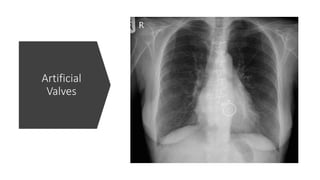

Artificial

Valves

ICU – Tubesand Lines